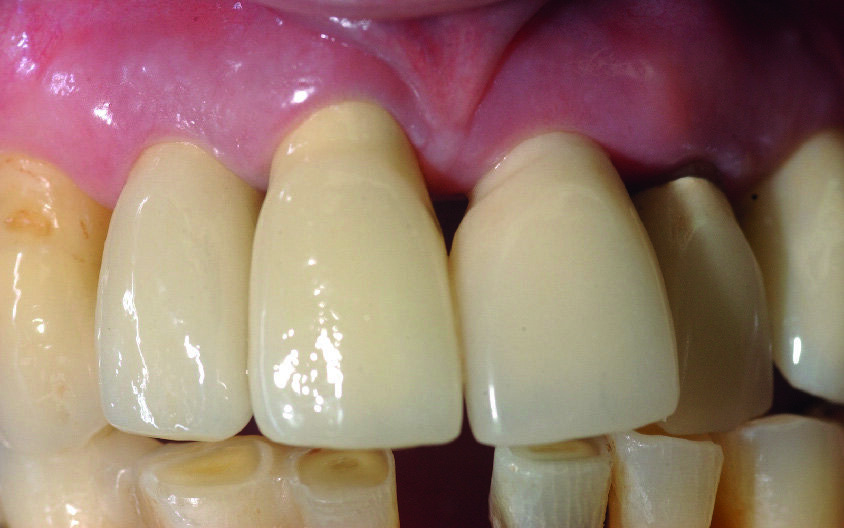

Me M. Ler, âgée de 71 ans lors de la chirurgie, ne présente pas d’antécédents médicaux particuliers, à l’exception d’un cholestérol stabilisé avec des statines (Tahor 10). Elle est traitée depuis 2007 pour une parodontite sévère qui est aussi globalement stabilisée cliniquement, radiologiquement et bactériologiquement. Nous avions déjà réalisé un traitement implantaire en 21 (2008) et 23 (2013) (Fig. 2). La patiente souhaite maintenant mettre des implants en 11 et 12 car les mobilités modérées de ces dents commencent à la gêner dans sa vie quotidienne.

Figs. 17a et b : Vues cliniques de face et palatine. Notez la bonne adaptation des tissus mous.

Les piliers implantaires en titane sont transvissés à l’aide d’une clé de repositionnement et d’une clé de serrage (Fig. 16). Les couronnes sont scellées en s’assurant qu’il n’y ait pas de débordement de ciment de scellement (Figs. 17a et b). Leur design ≪ parodontal ≫ permettra un bon contrôle de plaque, garant de leur pérennité à moyen et long terme. Une radio de contrôle permet de confirmer le bon positionnement de toutes les pièces prothétiques, ainsi que leur ajustement (Fig. 18).